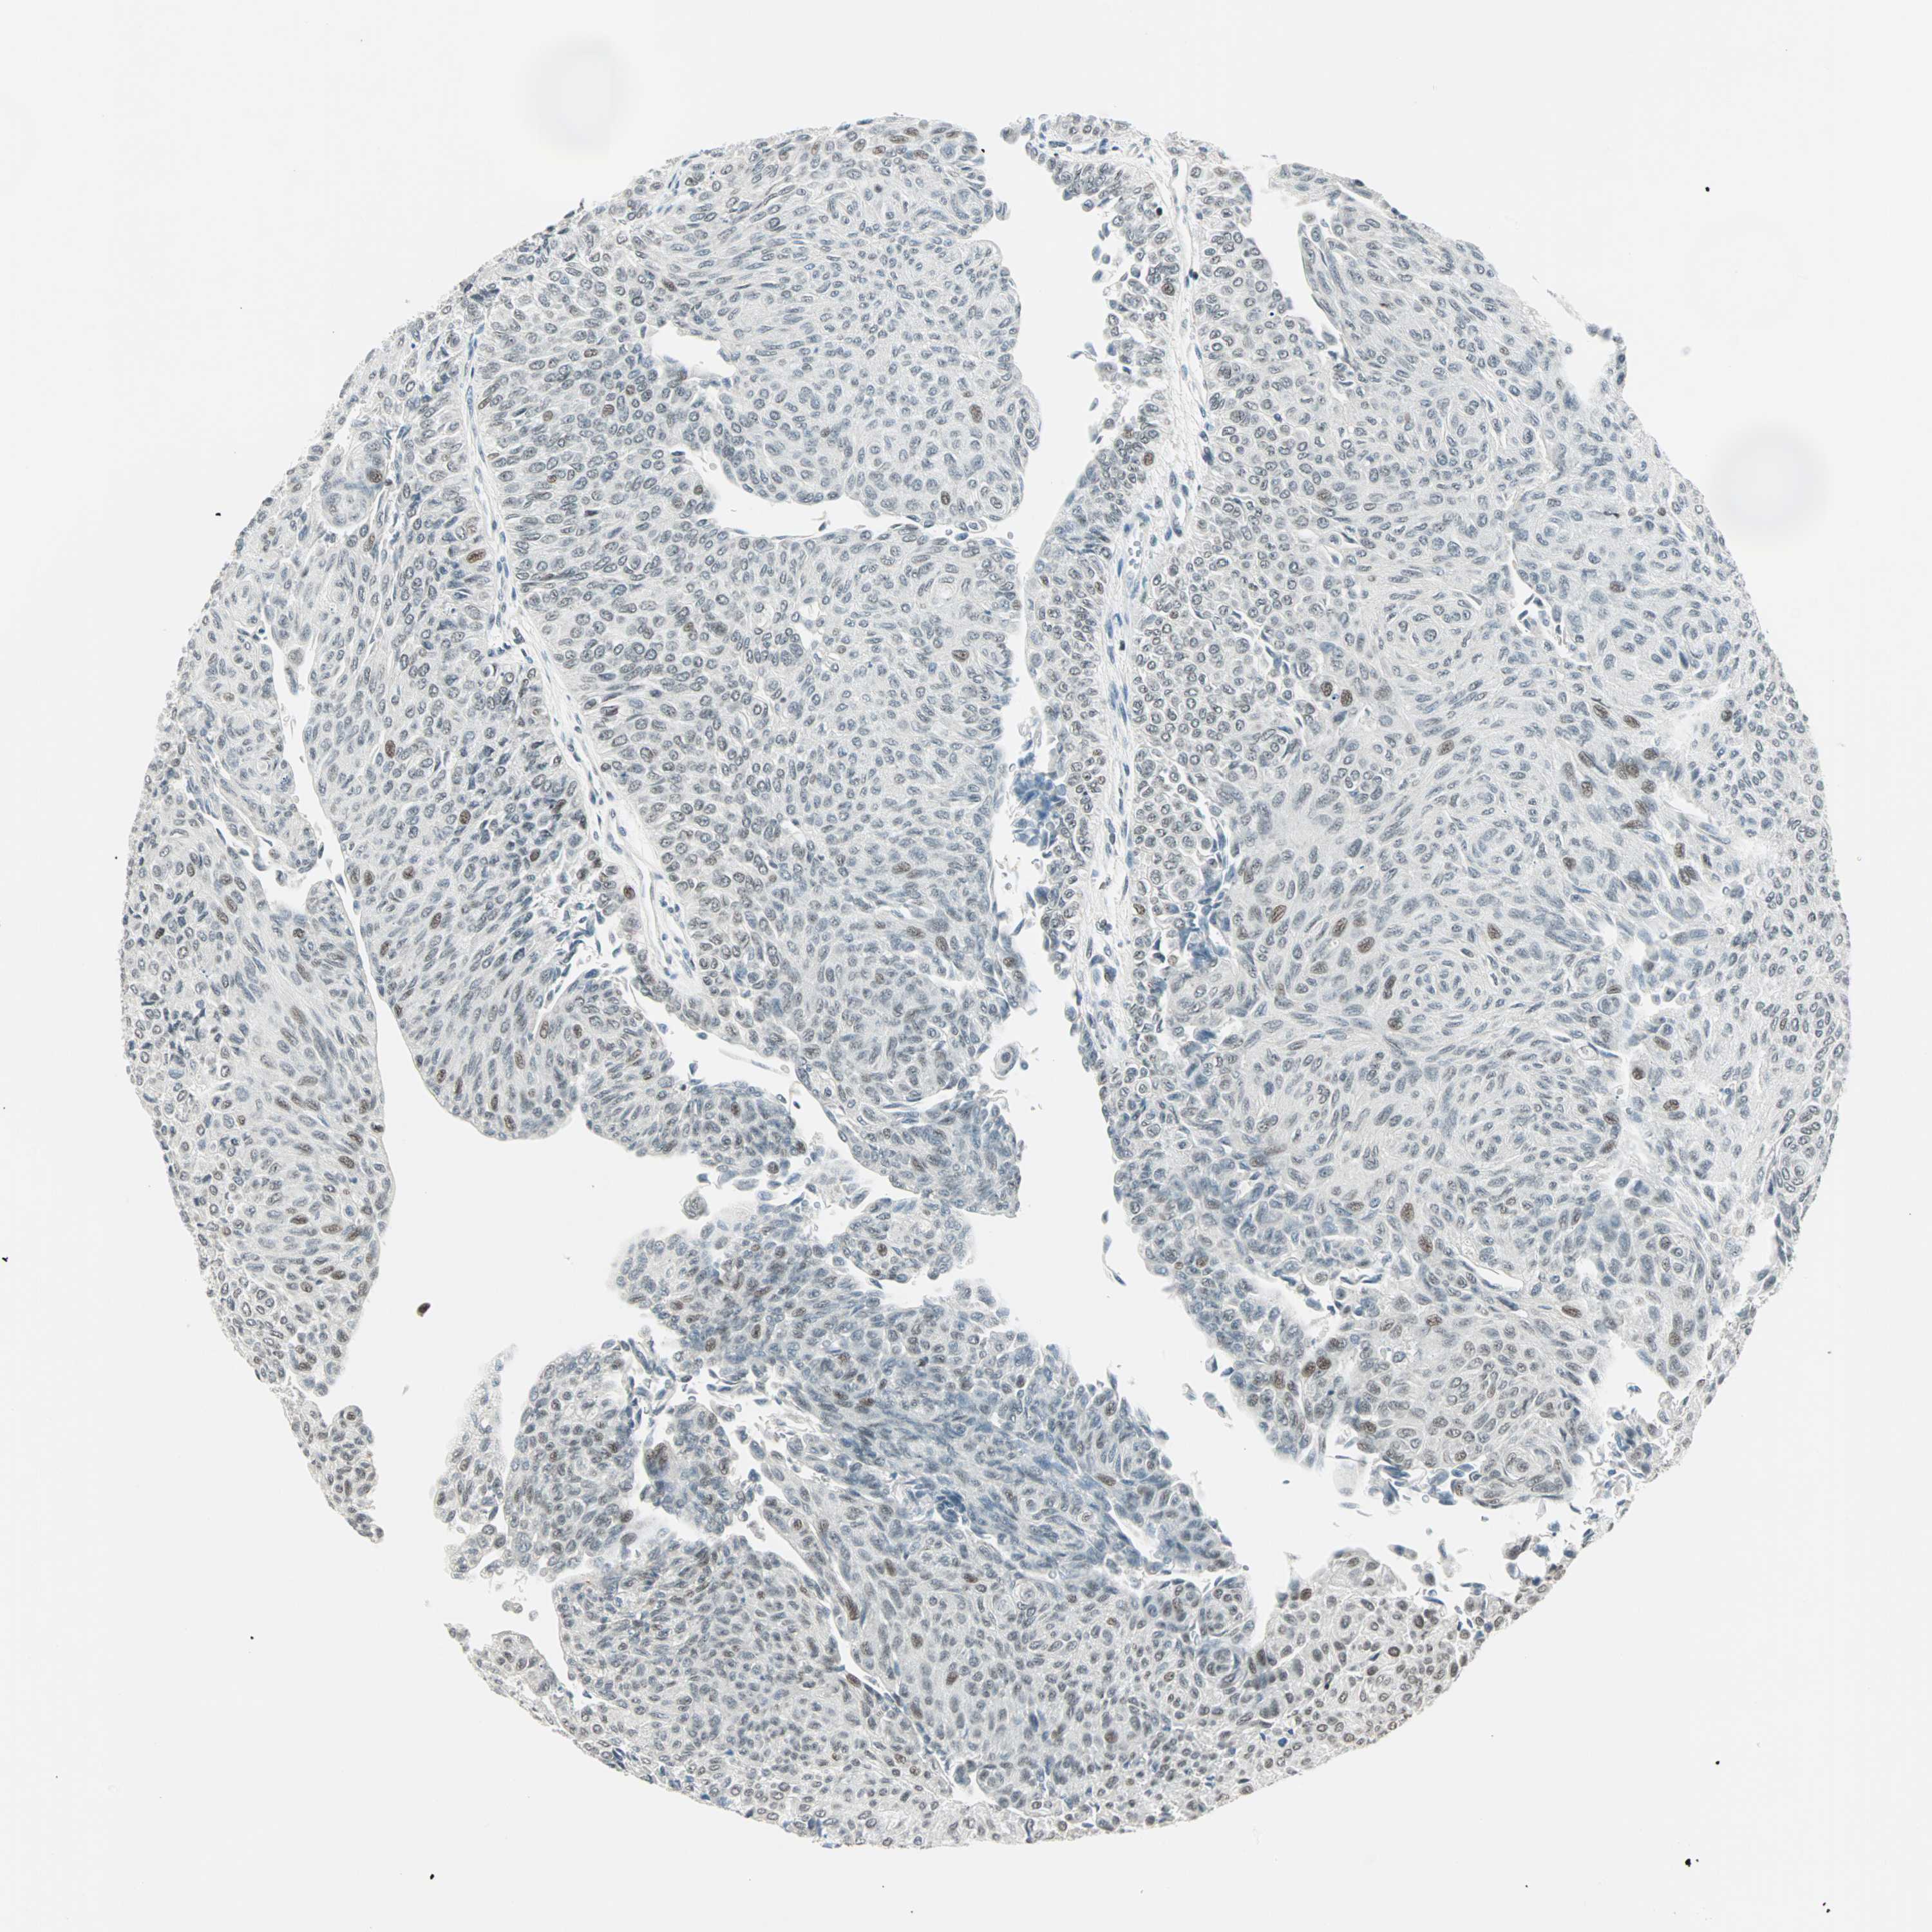

UROTHELIAL CANCER - Protein expressioni

A mouse-over function shows sample information and annotation data. Click on an image to view it in a full screen mode. Samples can be filtered based on level of antibody staining by selecting one or several of the following categories: high, medium, low and not detected. The assay and annotation is described here.

Note that samples used for immunohistochemistry by the Human Protein Atlas do not correspond to samples in the TCGA dataset.

Antibody stainingi

Antibody staining in the annotated cell types in the current human tissue is reported as not detected, low, medium, or high, based on conventional immunohistochemistry profiling in selected tissues. This score is based on the combination of the staining intensity and fraction of stained cells.

Each image is clickable and will lead to virtual microscopy that enables deeper exploration of all samples and also displays staining intensity scores, fraction scores and subcellular localization as well as patient and tissue information for each sample.

Antibody HPA047213

Antibody HPA062123

Antibody CAB004506

Urothelial carcinoma, High grade

Urothelial carcinoma, Low grade

Urothelial carcinoma, NOS